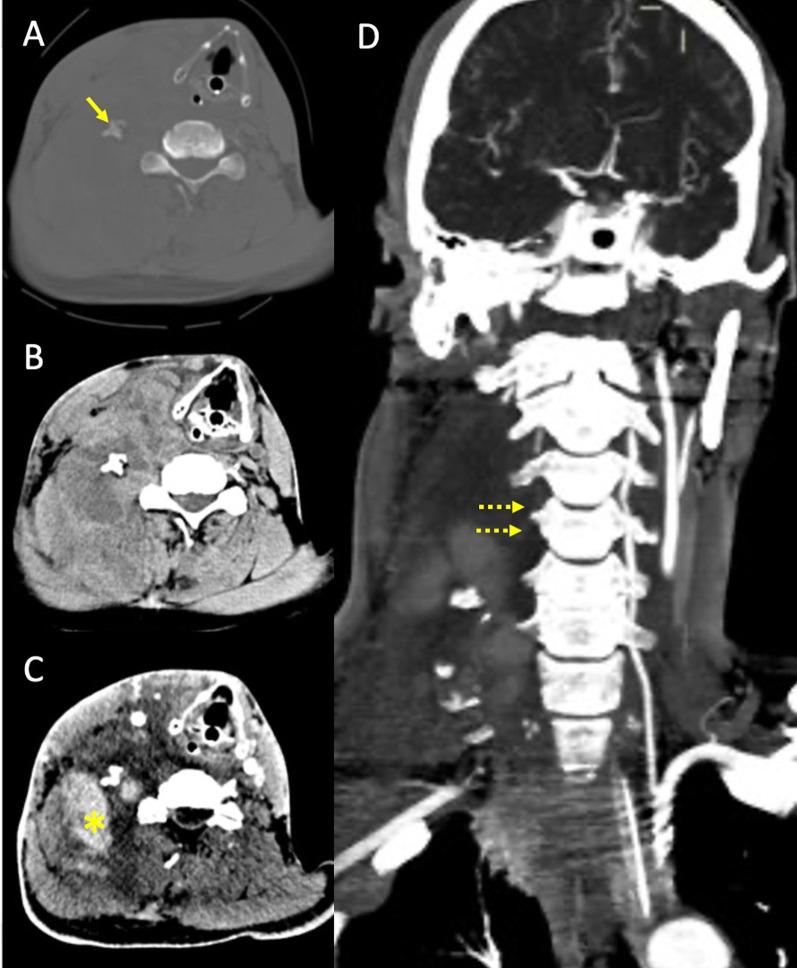

The objective of this work is to describe the possible cerebrovascular complications of critically ill traumatic brain injured patients and to understand the most common underlying mechanisms and radiological features as well as their management. A variety of pathological entities will be addressed, such as post-traumatic aneurysms, carotid-cavernous fistula, arterial occlusion, arterial dissection (in potential association with brain ischemia), as well as arterial rupture/avulsion and post-traumatic venous thrombosis. Neurovascular complications of head trauma vary depending on the traumatic mechanism, on the site of impact and on the osseous structures involved. Early diagnosis is mostly based on Computed Tomography/Computed Tomography Angiography (CT/CTA) whose findings help guide patient management by detecting vascular lesions potentially leading to neurological deterioration. Magnetic resonance imaging may be useful in selected cases. Today Digital Subtraction Angiography (DSA) is mostly a diagnostic problem-solving tool when CTA findings are equivocal but advanced endovascular interventional techniques have improved the therapeutic possibilities in post-traumatic vascular complications.  CONCLUSIONS: Neurovascular complications are not common after head trauma but should not be overlooked because they might lead to severe and life-threatening consequences. Early diagnosis, and a multidisciplinary collaboration including neuroradiologists, neurosurgeons and neurointensivists is fundamental in order to prevent and minimize secondary brain damage in this population.

这项工作的目的是描述重症创伤性脑损伤患者可能出现的脑血管并发症,并了解最常见的潜在机制、放射学特征及其治疗方法。将探讨多种病理实体,如创伤后动脉瘤、颈动脉海绵窦瘘、动脉闭塞、动脉夹层(可能与脑缺血相关),以及动脉破裂/撕裂和创伤后静脉血栓形成。头部创伤的神经血管并发症因创伤机制、撞击部位和所涉及的骨性结构而异。早期诊断主要基于计算机断层扫描/计算机断层扫描血管造影(CT/CTA),其结果有助于通过检测可能导致神经功能恶化的血管病变来指导患者的治疗。在某些特定情况下,磁共振成像可能有用。如今,当CTA结果不明确时,数字减影血管造影(DSA)大多是一种解决诊断问题的工具,但先进的血管内介入技术已改善了创伤后血管并发症的治疗可能性。